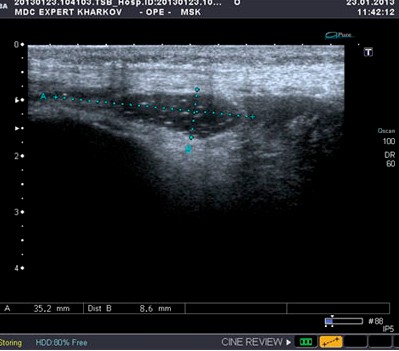

МРТ и УЗИ суставовУЗИ позволяет обнаруживать разрушение суставного хряща, выпот в суставные сумки, определять скопление жидкости в полости сустава, а также ее структуру и включения. Благодаря методике обнаруживаются дегенеративные изменения и воспаления, при применении дуплексного сканирования оценивают кровоснабжение пораженных участков. УЗИ имеет приоритетное значение в ранней диагностике аномалий развития тазобедренных суставов у детей младше 3 месяцев, поскольку до этого возраста воздерживаются от проведения рентгенографии.